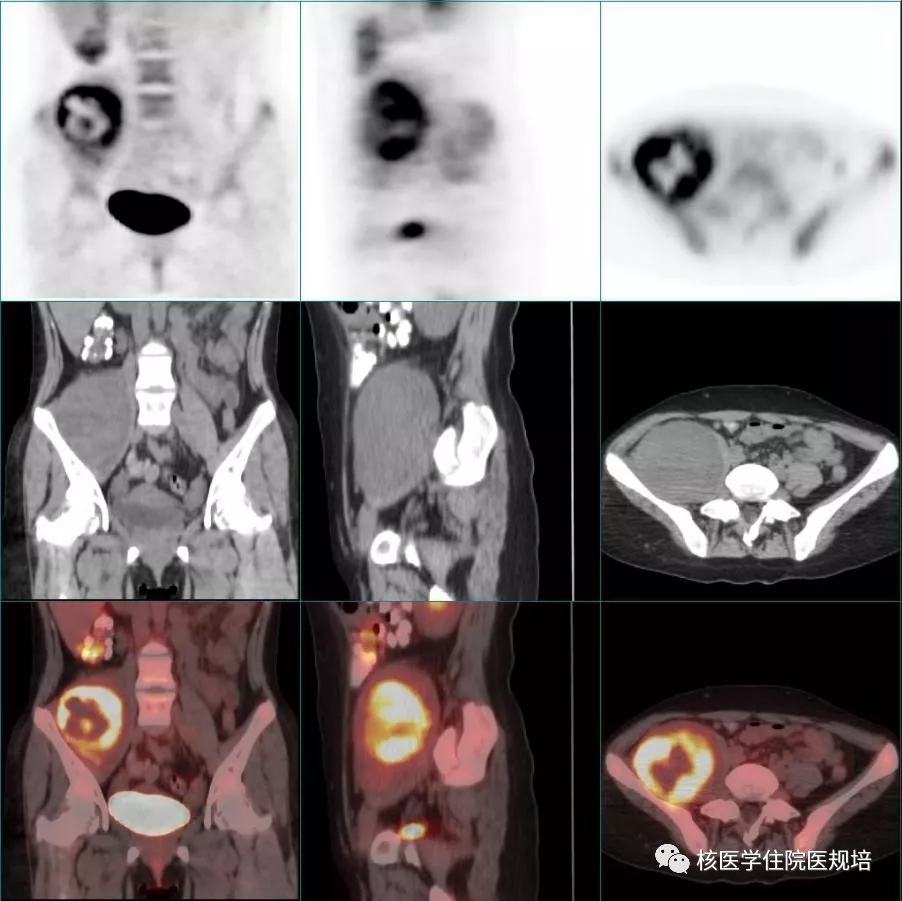

患者女性,16岁,半个月前无明显诱因出现右腿疼痛,外院盆腔平扫CT示右髂窝可见一个类圆形软组织肿物,邻近腰大肌受压;骶骨骨质破坏伴软组织肿物形成,考虑恶性病变可能。于外院行骶骨肿物穿刺活检,病理提示神经纤维瘤可能。查体:皮肤上多发雀斑及牛奶咖啡斑(图1);背部皮下可触及一结节,直径约1.0cm。追问家族史,其父亦有相同皮肤改变。综合患者影像及查体结果,临床考虑为神经纤维瘤病可能性大,为进一步明确病变范围性质18F-FDG PET/CT显像(图2)。

右侧髂窝可见一类圆形软组织密度肿物,FDG摄取不均匀增高(SUVmax:8.7),其内可见放射性稀疏区,肿物大小约7.7×7.8×12.6cm,右侧腰大肌受压,邻近髂骨未见明显异常(图3);骶骨骨质破坏,可见软组织肿块沿骶孔向外生长,最大截面约8.2×5.3cm,FDG摄取增高(SUVmax:6.6)(图4);双侧背侧胸壁(向肺内生长)各见一软组织密度肿物,大小分别为4.0×2.1cm、1.8×0.8cm,较大者FDG摄取增高(SUVmax:2.9),邻近肋骨受压(图5)。T10椎体后方及左侧臀部皮下软组织内可见多发类圆形软组织密度结节,直径分布在0.4-1.0cm,较大者位于T10椎体后方,FDG摄取增高(SUVmax:1.1)(图6和图7)。右侧颈动脉鞘周围可见一类圆形软组织密度灶,直径约1.5cm,FDG摄取轻度增高(SUVmax:2.5)(图8)。扫描范围其余部位未见明显异常。

全身多发软组织结节及肿物,部分FDG代谢增高,符合多发神经纤维瘤病表现,其中右髂窝和骶骨病灶FDG代谢显著增高,考虑恶变可能性大。

本例患者为年轻女性,此次以发现盆腔肿物就诊,穿刺病理提示神经纤维瘤可能,查体可见全身多发牛奶咖啡斑、皮下结节,且其父有类似皮肤表现,不难诊断NF1,完善PET/CT显示病变多发累及右颈部、双侧胸壁、右髂窝、骶骨及皮下,呈边界清晰、形态规整的软组织肿物影,有沿神经干走行分布的特点,病变邻近骨质受压或呈膨胀性改变,符合多发性神经纤维瘤的CT表现,但病灶FDG摄取程度不一,右髂窝和骶骨病灶FDG摄取显著增高,高度提示恶变可能,并被最终病理证实。但在之前的穿刺活检中并没有提示恶变的倾向,这可能与取材部位有关。因此本病例也提示临床,若在PET/CT引导下选择FDG代谢增高的部位进行穿刺活检,可提高诊断准确性,尤其是对于高危人群。